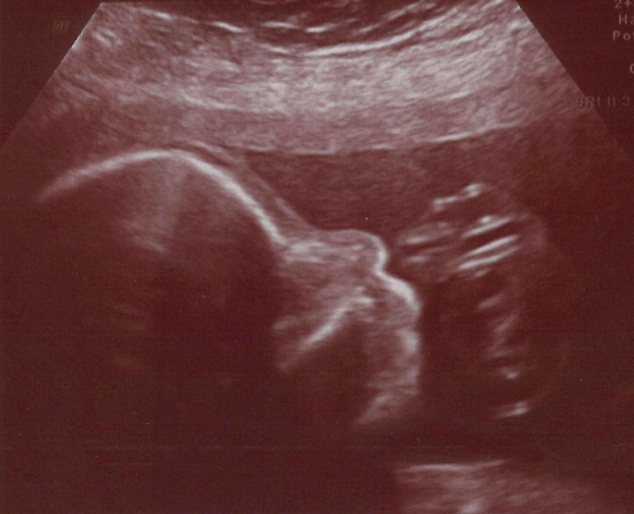

Según comentan en la clínica parece que ya hace Air guitar.

Por lo pronto parece futbolista, por las patadas que da, o sí, podría ser Air guitar, pero.

Dando saltos a lo Eddie van halen.